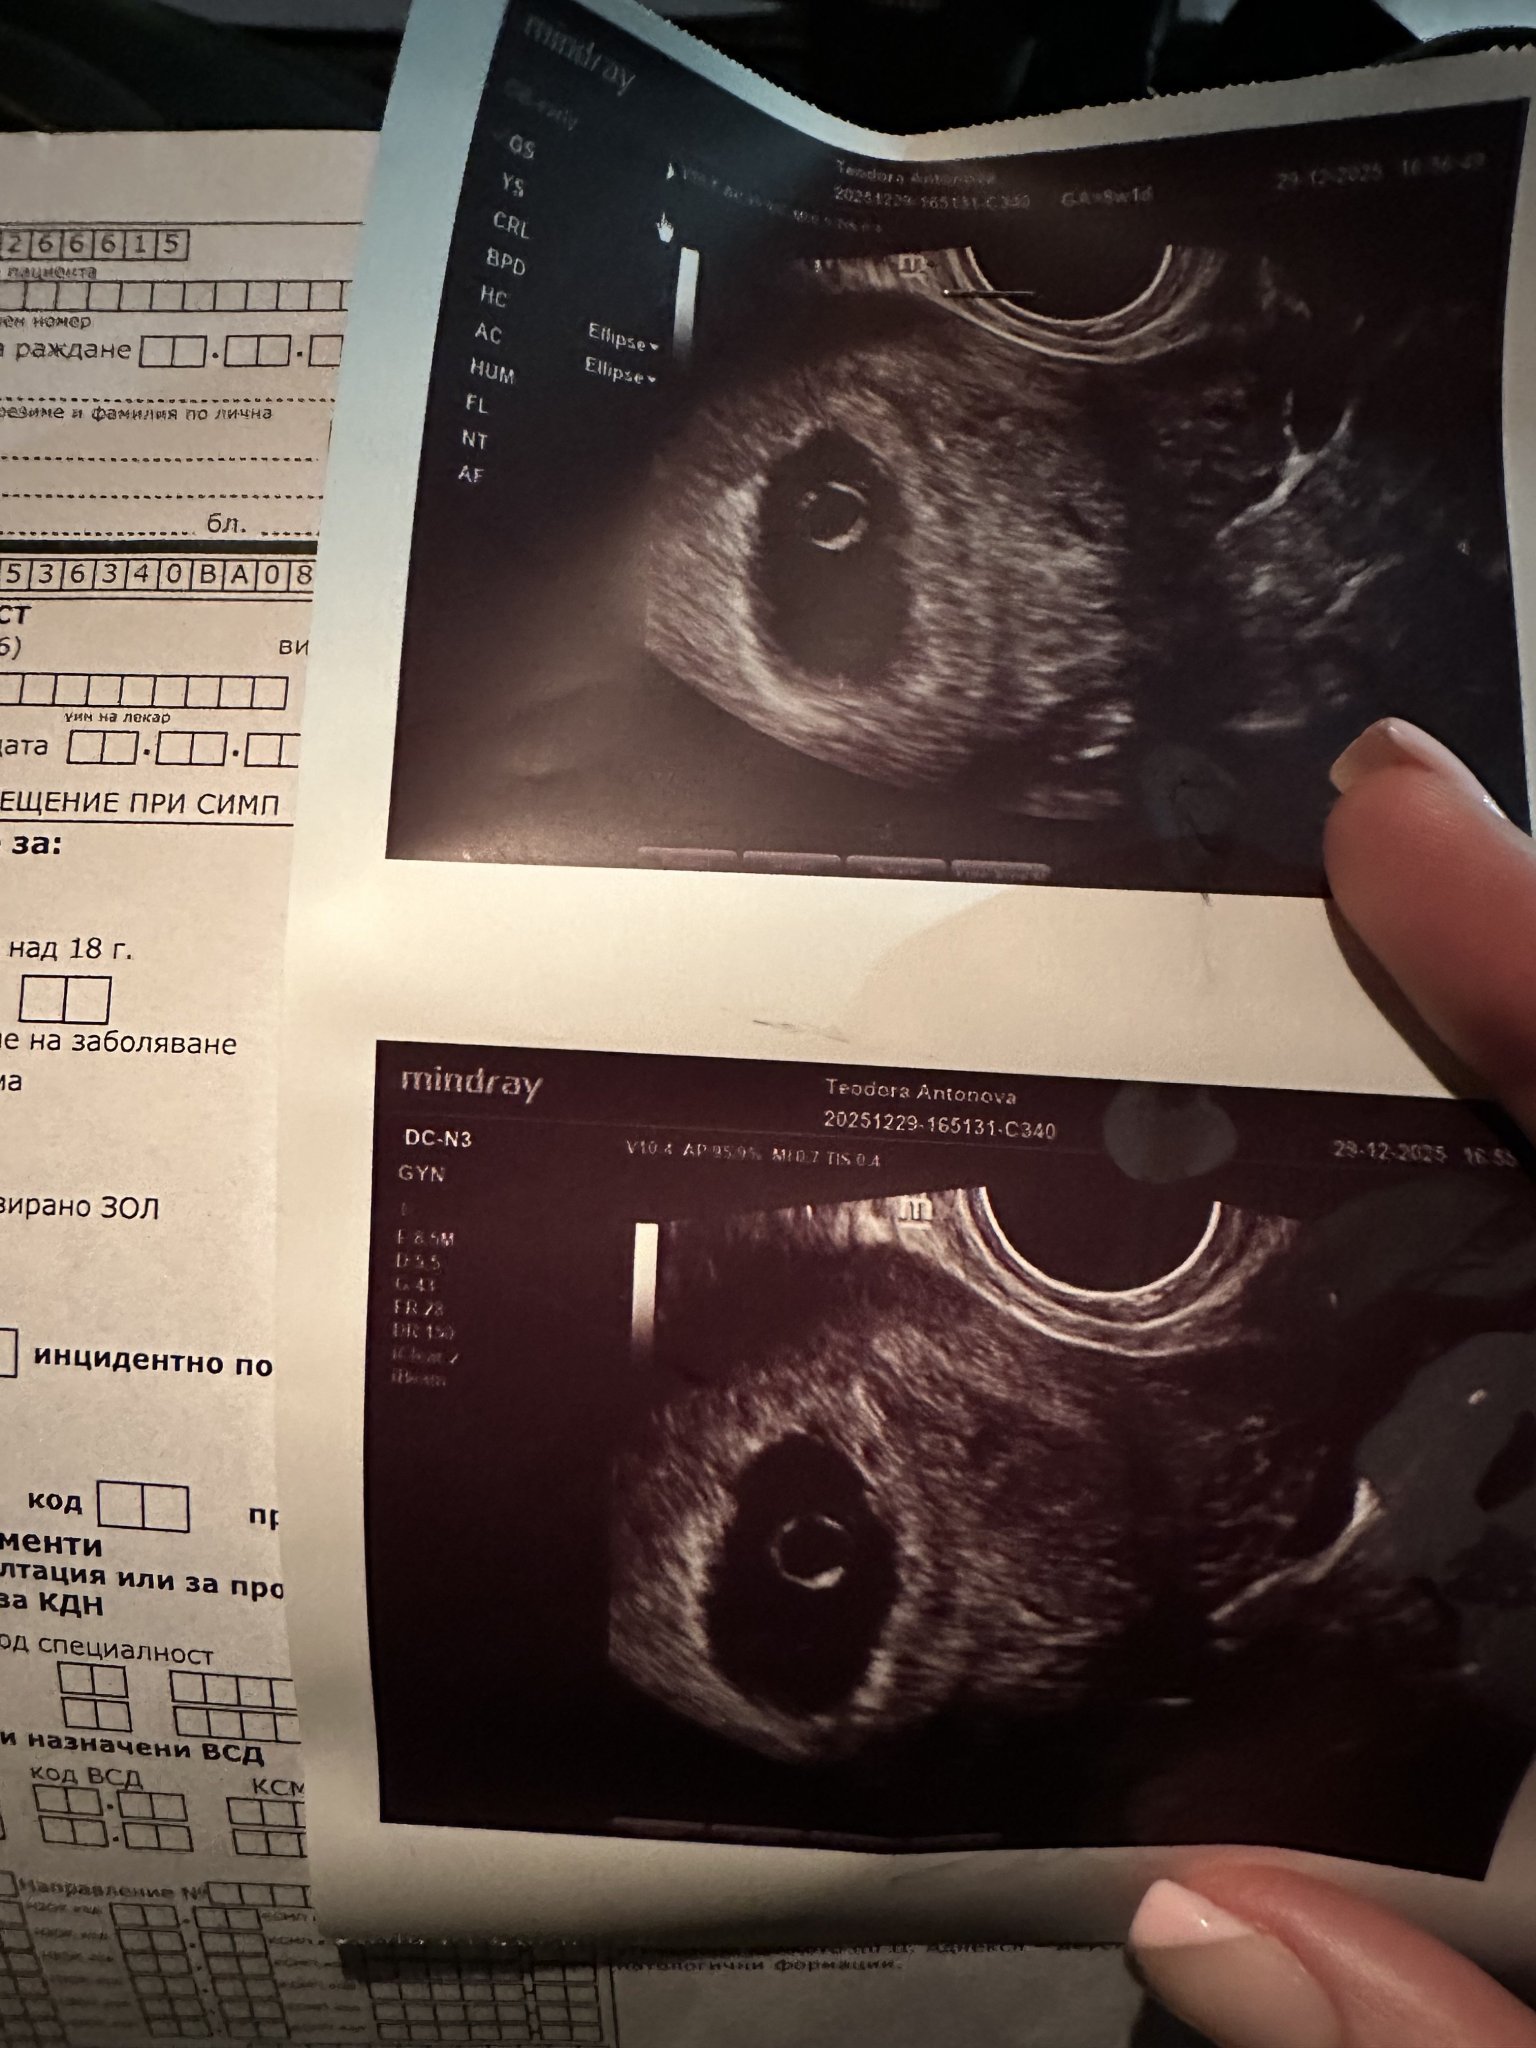

Здравейте мамита на 1-ви декември разбрах,че съм бремнна, вчера бях на втори преглед и видяха,че имам сакче, но няма ембрионче! Последния ми цикъл беше на 2 ноември, с овулацията на 16 ноември, ходих след това на второ мнение и те не видяха ембрионче! На един е преглед ме водят 6+6, а на другия 8+1 на 1-ви декември пуснах кръвни и ми излезна 208 mIU

Вчера на 29-ти пак пуснах кръвни 53390 mIU, сега и на 31-ви ще пусна отново! нямам кървене нямам болки,( но ми пуснаха направление за абсорт) Ще пробвам да прикача ехографски снимки

Благодаря, но трима доктора казват,че съм за аборт, други двама,че всичко е нормално в малка седмица съм!

От тук нататък водещо е какво се вижда на ехограф. Ако след една седмица все още няма развитие, значи бременността не се развива. Не е задължително да имате болки и кървене. При задържан аборт бременността не се развива, но тялото не изхвърля ембриона и следователно трябва да се пристъпи към МА или кюртаж.

В 7-8 седмица трябва да има вече сърдечна дейност, не е толкова "малка" седмицата. Освен ако не си с късна овулация и гестационната възраст не е реална, но при всички положения, поне точица ембрионче трябваше да се вижда в сака. Frowning1